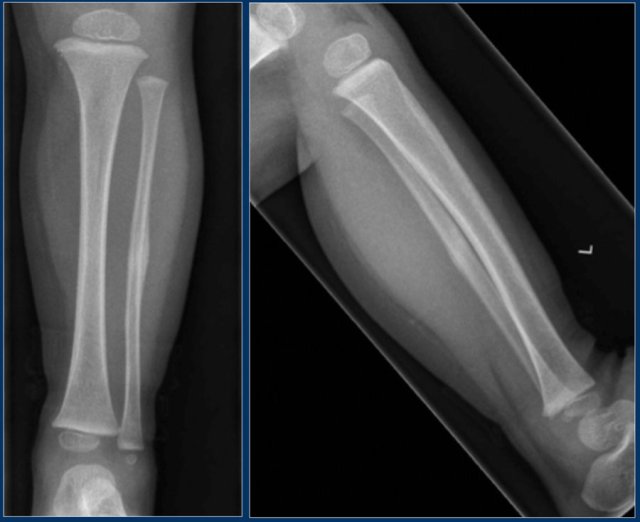

On x-ray there is a sharp defined oval lytic lesion with or without a sclerotic rim, with its long axis parallel to the long axis of the bone (see figure).

On MRI the lesion is hyperintense on T2WI. There is joint effusion and only minimal edema in the surrounding musculature.